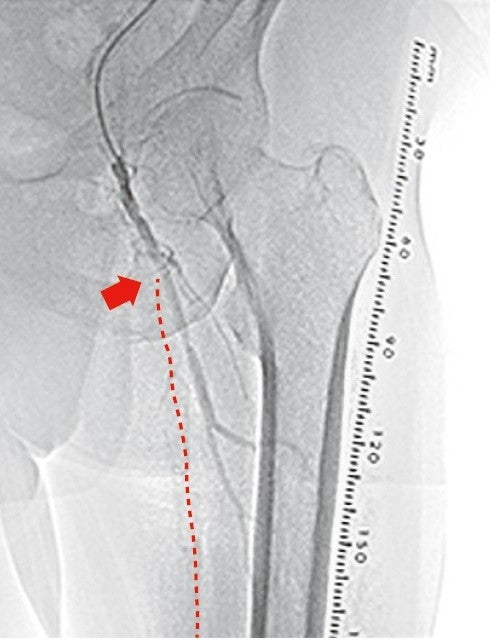

右大腿動脈穿刺、0.035 inchワイヤーを用いて、ガイディングシース 6 Fr 60 cmを左外腸骨動脈まで誘導し、造影を行った(図1.2)。体表面エコーガイドのもと、マイクロカテーテルと0.014 inch フロッピー300 cmワイヤーで、確実に浅大腿動脈入口部から血管真腔内を進めた。0.014 inch フロッピー300 cmワイヤーを抜去し、血管狭窄部貫通用カテーテルに交換し、閉塞部位を慎重に進め、貫通に成功した。血管狭窄部貫通用カテーテルにエクステンションワイヤーをつなげ、マイクロカテーテルを抜去、0.018 inchの径 2.0/長 20 mmバルーンで閉塞部位を拡張した。マイクロカテーテルを末梢まで進め、血管狭窄部貫通用カテーテルを抜去、0.014 inch 300 cm ワイヤーに交換、血管内超音波で病変部の観察を行った。ほぼ真腔を捉えていることが確認できたため、径 4.0/長 250 mmバルーンで閉塞全域を拡張した。一部石灰化病変により、拡張不良部位を認めたため(図3)、径 3.0/長 40 mm ノンコンプライアントバルーンで追加拡張を行った。再度、径 4.0/長 250 mmバルーンで閉塞全域を拡張した(図4)。血管内超音波で閉塞領域を観察し、ほぼ真腔を捉えていることが確認できた。ついで、径 5.0/長 250 mmバイアバーン® ステントグラフトを留置し、グラフト内をバルーンで後拡張した。血管内超音波でグラフト拡張および浅大腿動脈入口部を確認した(図5.6)。結果、左浅大腿動脈の良好な血流を得た(図7)。